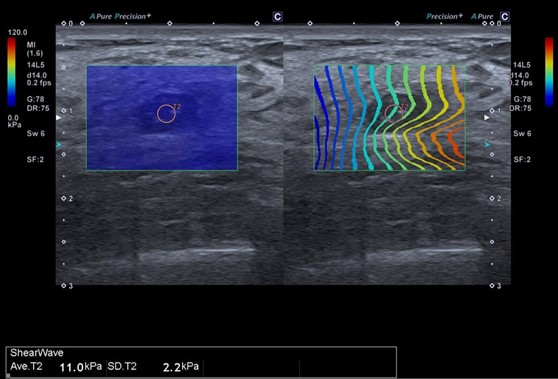

Еластометрія (2D-SWE Aplio) у дітей — рекомендації  для лікаря

1. Що таке 2D-SWE?

Метод кількісного вимірювання жорсткості печінки за допомогою ультразвуку з відслідковуванням швидкості зсувних хвиль у режимі реального часу. Дає оцінку фіброзу без інвазивної біопсії.

4. Техніка виконання

• Візуалізувати печінку в B-режимі без тіней від ребер чи легень.

• Датчик перпендикулярно до капсули.

• ROI (region of interest; ділянка інтересу) розташовувати 15–20 мм нижче капсули печінки, уникати судин та жовчних проток.

• 3–5 вимірювань у одному й тому самому місці (не рухати датчик).

• Дихання — спокійне або затримка на вдиху (за можливості).

ВікСередня (кПа)Верхня межа норма

3-5 р.3,6-4,1

6-8 р.3,75-4,6

9-11 р.3,77-4,6

12-15 р.3,74-4,9

Загальні3,5-4,0до 5, 0

Значення >5 кПа — фіброз можливий,

>9 кПа — можлива компенсована просунута хвороба печінки (cACLD – Compensated Advanced Chronic Liver Disease),

>13 кПа — висока ймовірність компенсованої просунутої хвороби печінки (cACLD)

>17 кПа — клінічно значима портальна гіпертензія (CSPH – Clinically Significant Portal Hypertension).